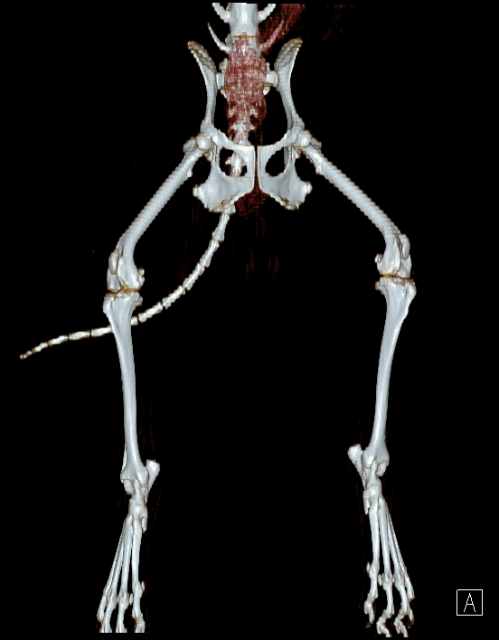

빠른 촬영속도를 통해 마취시간을 최소화 하며, 선명한 3차원 영상을 구현합니다.

종양, 전이평가, 선천적 혈관 기형 등 여러 질환의 조기 발견 및 환자상태를 평가합니다.

골절, 골종양 등